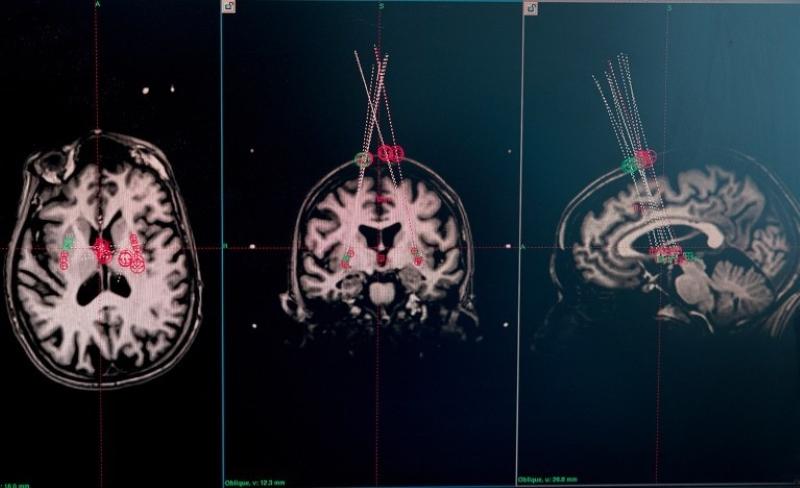

關于癲癇的研究同樣值得關注。在美國神經元治療公司開展的臨床試驗中,外科醫生借助干細胞療法,將干細胞整合到15名癲癇患者的神經回路中。移植一年后,其中兩名參與者嚴重癲癇發作的頻率幾乎降至零,且效果已經持續了兩年。其他大多數參與者的癲癇發作頻率也顯著降低。該公司報告稱,這一療法沒有明顯副作用,也沒有造成認知損傷?;谏鲜鲂Ч?,包括神經元治療公司在內的團隊打造的“有效干細胞療法”,也被《麻省理工技術評論》評為2025年“十大突破性技術”之一。